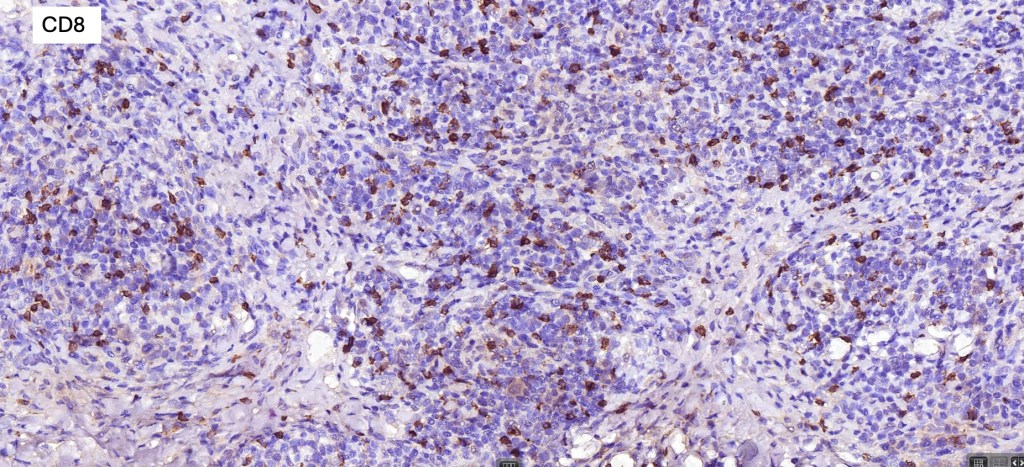

Immunohistochemistry

•Clonal T-cell receptor rearrangement is supportive but not diagnosis of mycosis fungoides as it may be seen in a variety of inflammatory dermatoses

•TCRβ, CD45RO, IL-2R, CLA, CD25, CD2, CD3, CD4, CD5, CD7 +ve

•Much less often CD8+ve

•Variable loss of CD5 (supports the diagnosis) & CD7 (not so helpful as also seen in inflammatory dermatoses)

.TCRγ, TIA, granzyme & EBER -ve